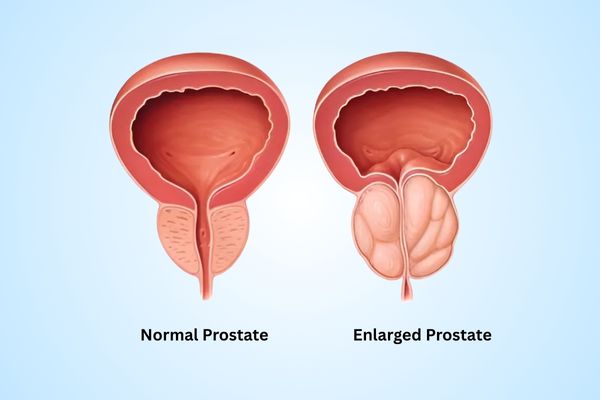

Anil S

Dr. Omang is truly a master in robotic surgery. My prostate treatment was smooth, and his post-surgery care was exceptional. The precision and recovery speed amazed me.